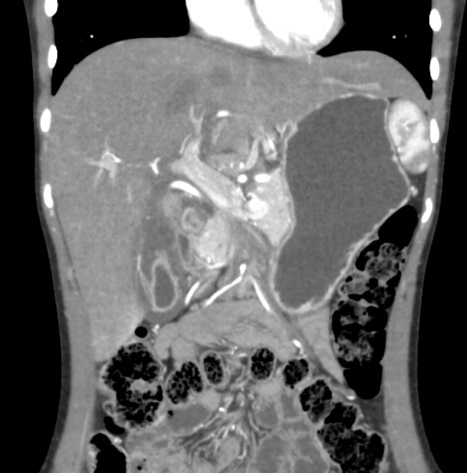

Hepatite aigue : Aspect de

hypodense region perioportale et peri hillaire du

foie ( >5mm ) . Image de hypodense de la parenchyme

du foie . Lymphadenopathie hillare dans ce cas est

en bien se voyait . Image radiologique du foie

en coupe TDM axiale . |

|

Aspect hypodense du

parenchyme du foie dansd hepatite aigue . Le

foie est en moins densite que la rate . Et image de

hypodense region periportale et image de

adenopâthie hileire du foie . |